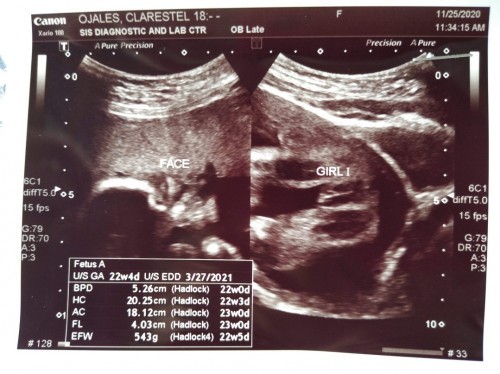

mga momsh kita nyo naman po diba sobrang linaw ng CAS utz ko? kitang kita nyo po na baby girl siya?hehe curios lang po ako sa mga nagsabe saken na wag daw muna ako kampante sa gender ni baby kasi baka daw mali. Means baka pag labas daw ni baby, baby boy siya😅 ano sa tingin nyo mommy? #firstbaby #advicepls #1stimemom #theasianparentph